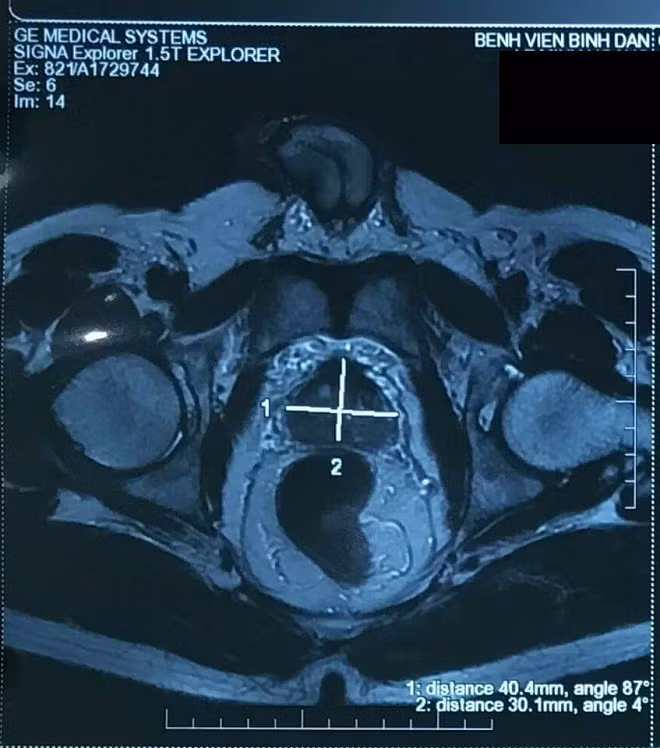

Kết quả sinh thiết cho thấy ông D. bị ung thư tuyến tiền liệt. Ngoài ra, ông D. được chụp cộng hưởng từ (MRI) và hình ảnh cho thấy khối choán chỗ lan toản toàn vùng ngoại biên, chưa xâm lấn túi tinh hai bên, chưa xâm lấn vỏ bao. Rất may mắn, kết quả xạ hình xương cũng chưa ghi nhận bất thường.